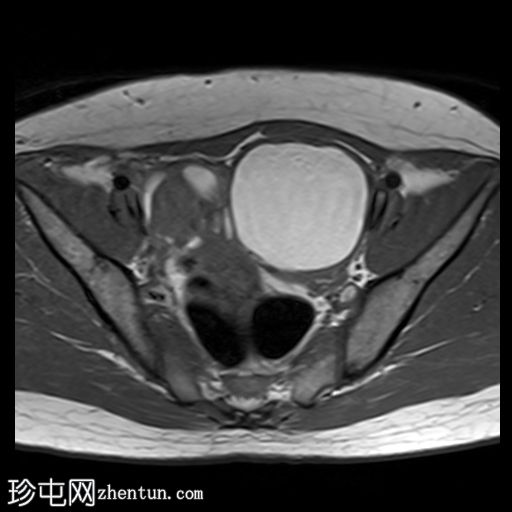

轴位

T1加权像

左侧卵巢可见一巨大、无强化囊性病变。该病变壁薄,在T1加权像和T1脂肪抑制像上呈均匀高信号,在T2加权像上呈独特的阴影状,符合子宫内膜异位囊肿的特征。值得注意的是,该病变可见两个增强灶,但未见内部实性成分或对比增强。

此外,右侧卵巢内数个小的、无强化囊性病变表现出类似的信号特征,这也符合子宫内膜异位囊肿的特征。

右侧卵巢内还有另一个囊性病变,在T1加权像上呈低信号,在T2加权像上呈高信号,并可见液平面。该病变无对比剂强化,可能代表出血性黄体囊肿。

双侧卵巢向内侧移位,形成“接吻卵巢征”。

子宫后壁子宫圆锥增厚,累及直肠前壁。

子宫圆韧带增厚。

子宫、双侧卵巢和直肠因挛缩性粘连/纤维带而靠近,形成近期描述的深部盆腔子宫内膜异位症的“三叶草征”。